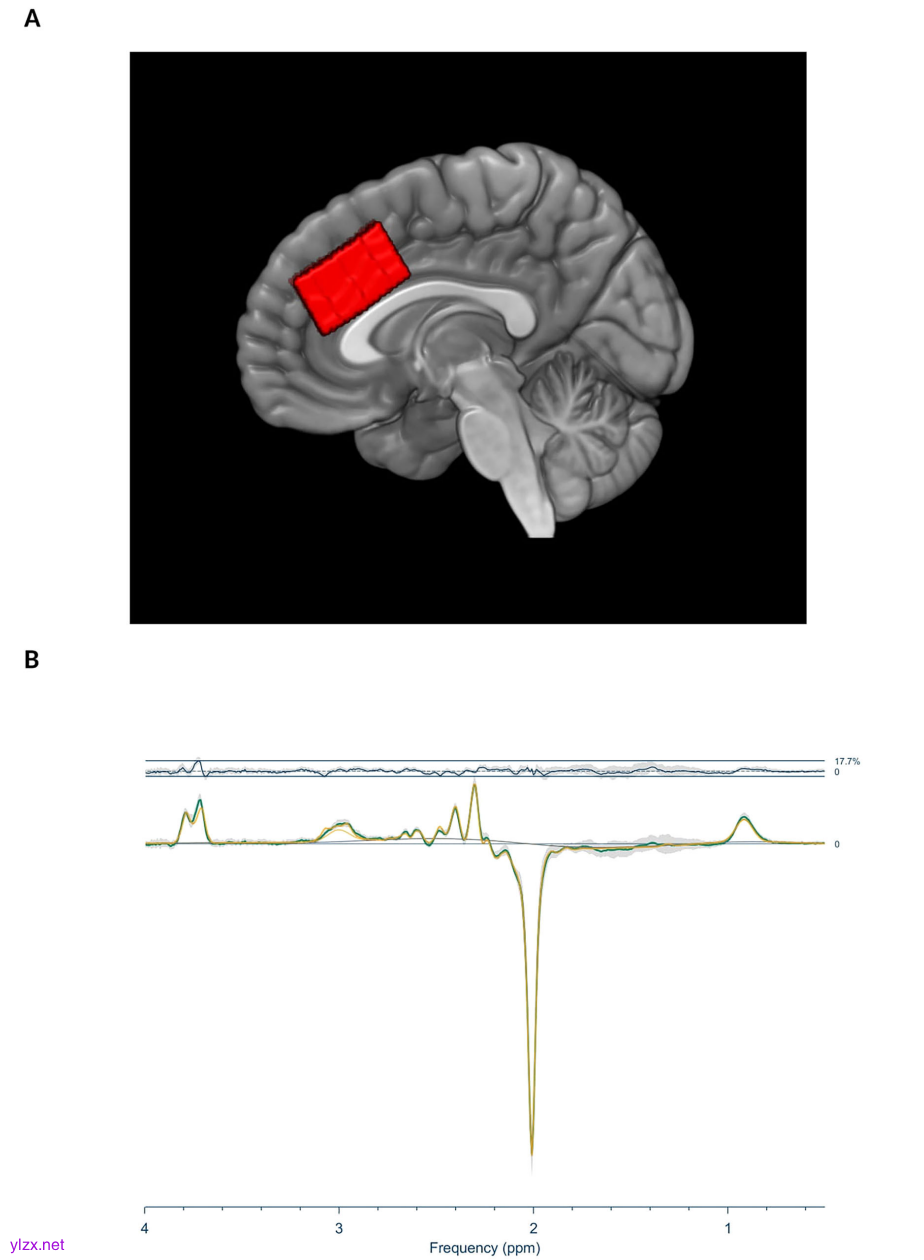

图1:体素定位和基线差异光谱

研究采用了一项双盲、假手术对照的临床试验设计,共纳入42名双相或单相抑郁症患者。所有患者在治疗前后均接受了MRS检测,以评估背侧前扣带回皮层(dACC)中的GABA和谷氨酸水平。其中28名患者还接受了[11C]氟马西尼PET扫描,用于测量全脑及特定脑区(如伏隔核和dACC)的GABA受体可用性。临床症状通过自评版蒙哥马利-阿斯伯格抑郁量表(MADRS-S)进行评估。iTBS治疗靶点为背内侧前额叶皮层(dmPFC),治疗参数为90%的静息运动阈值,每天两次,持续10至15个工作日。假手术组通过屏蔽线圈和同步电刺激模拟真实治疗的感觉,以排除安慰剂效应。